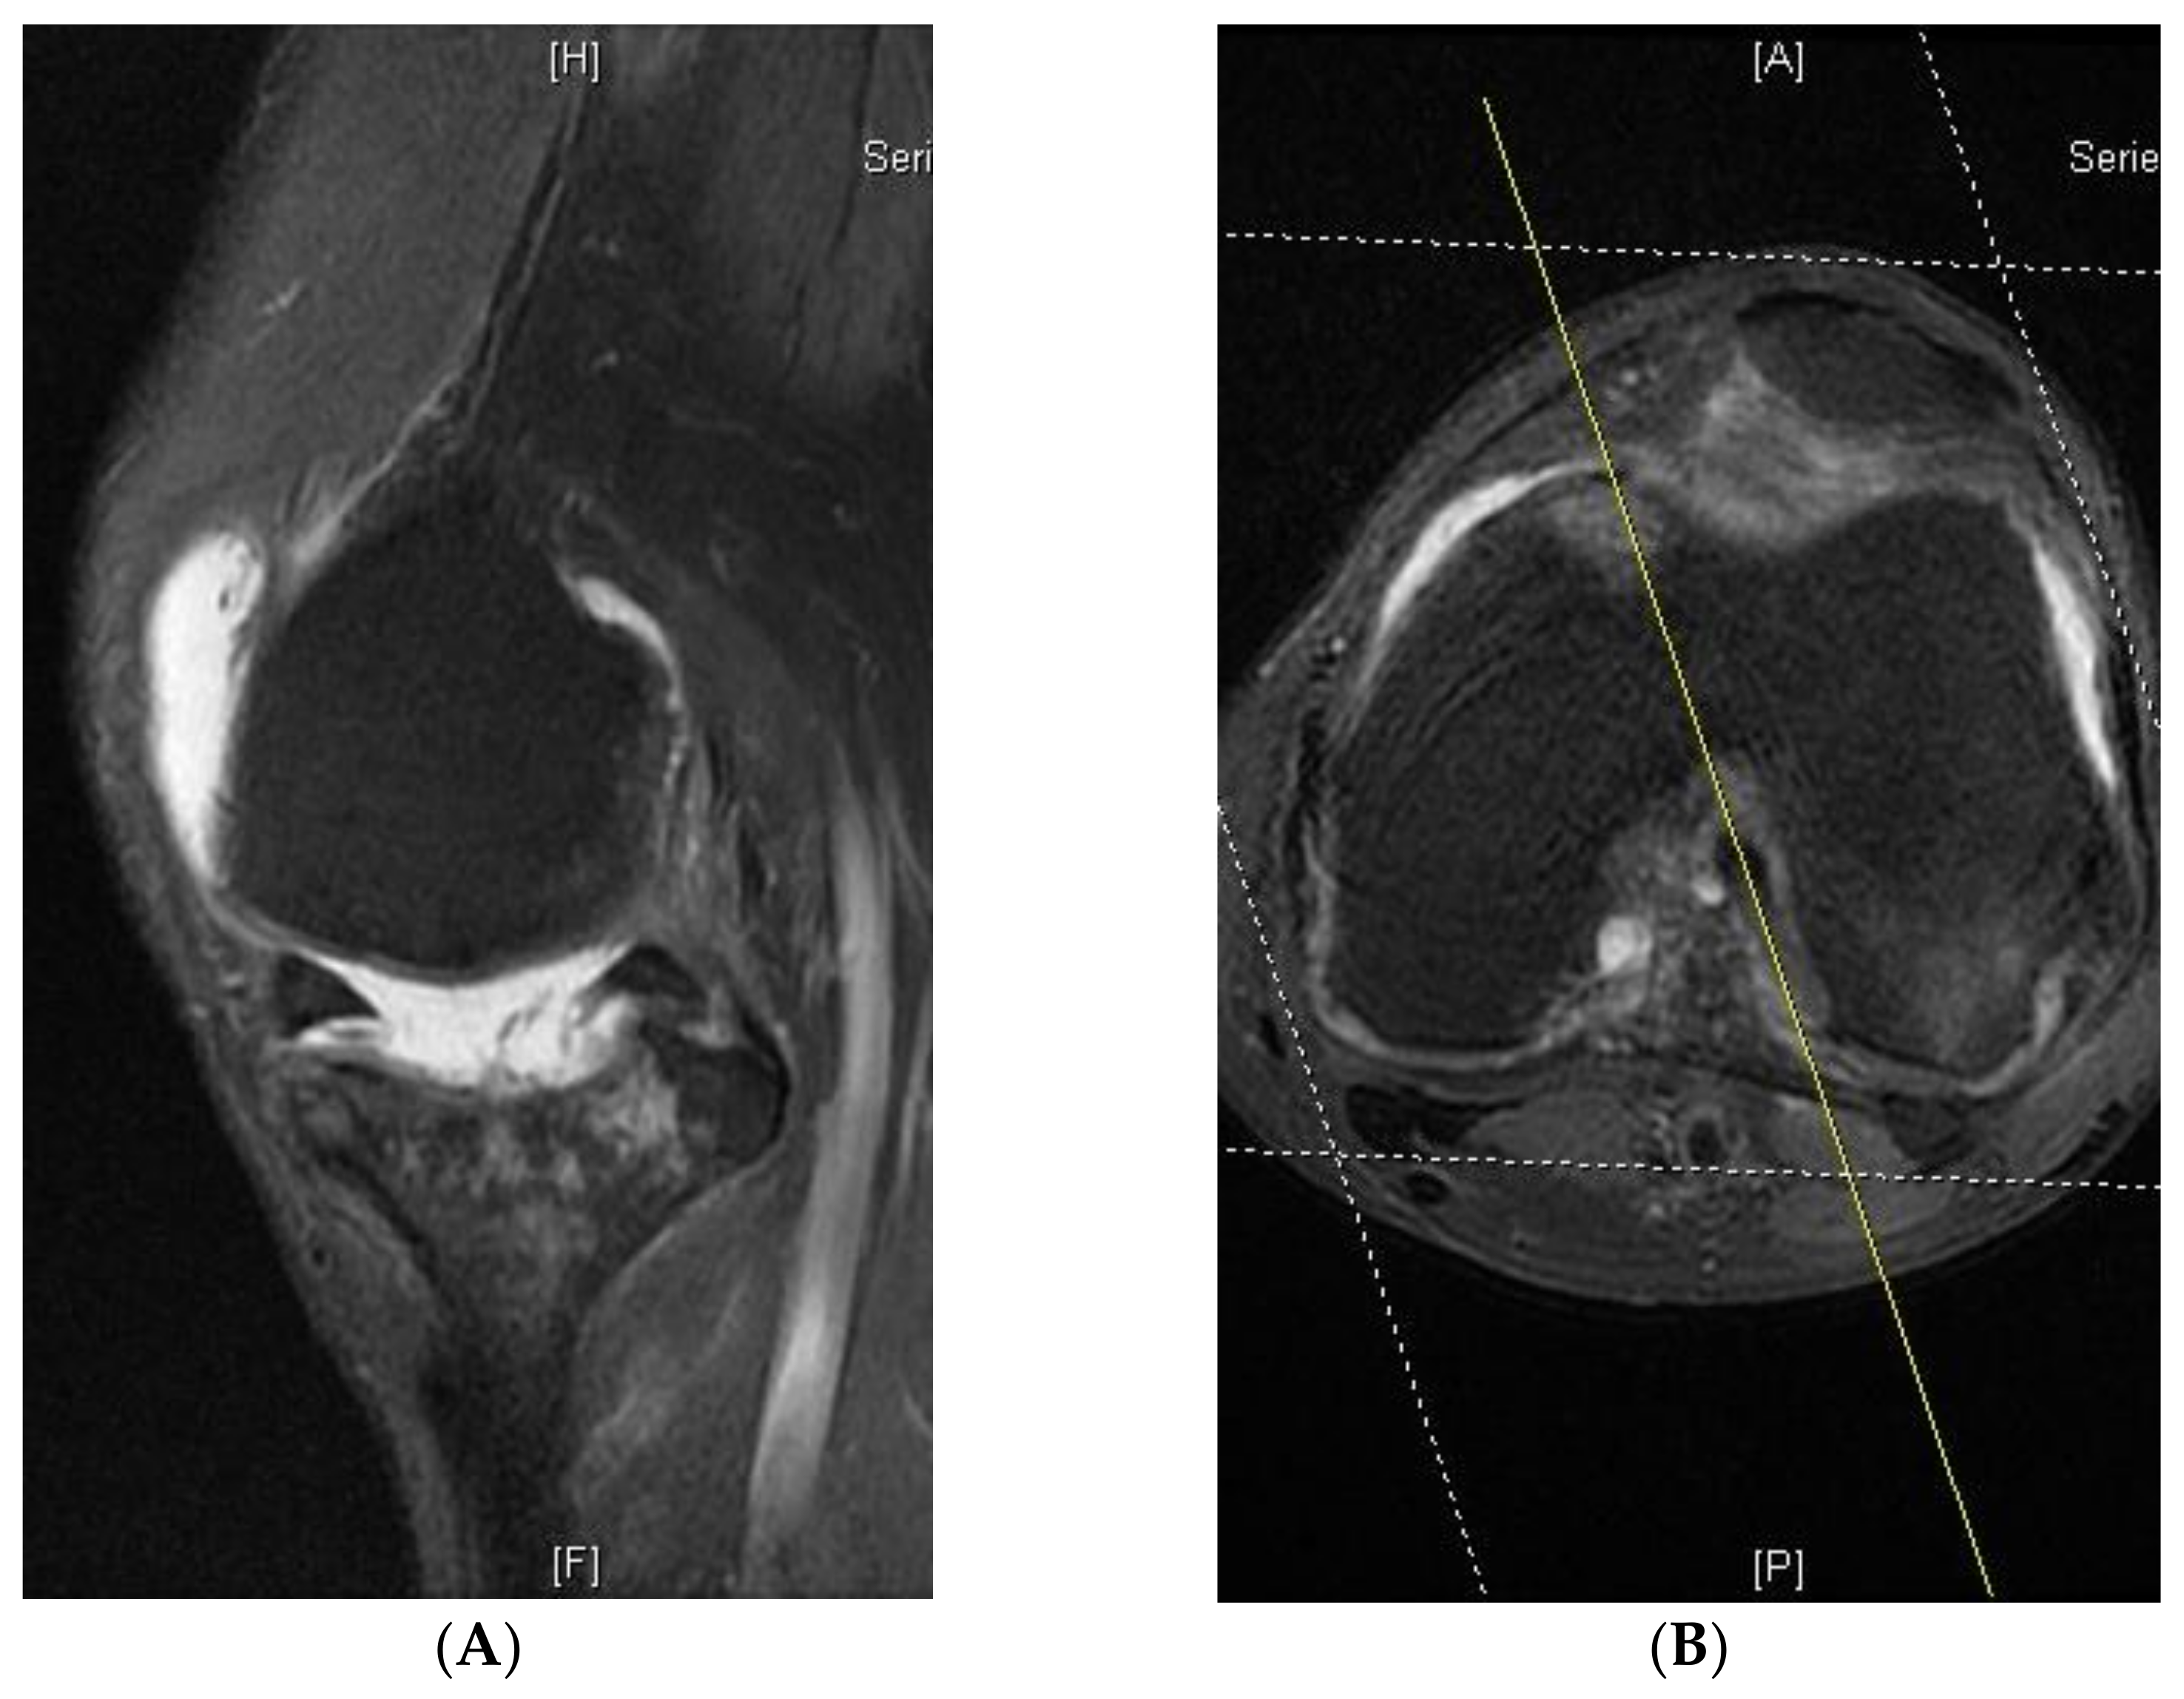

2. Materials and Methods